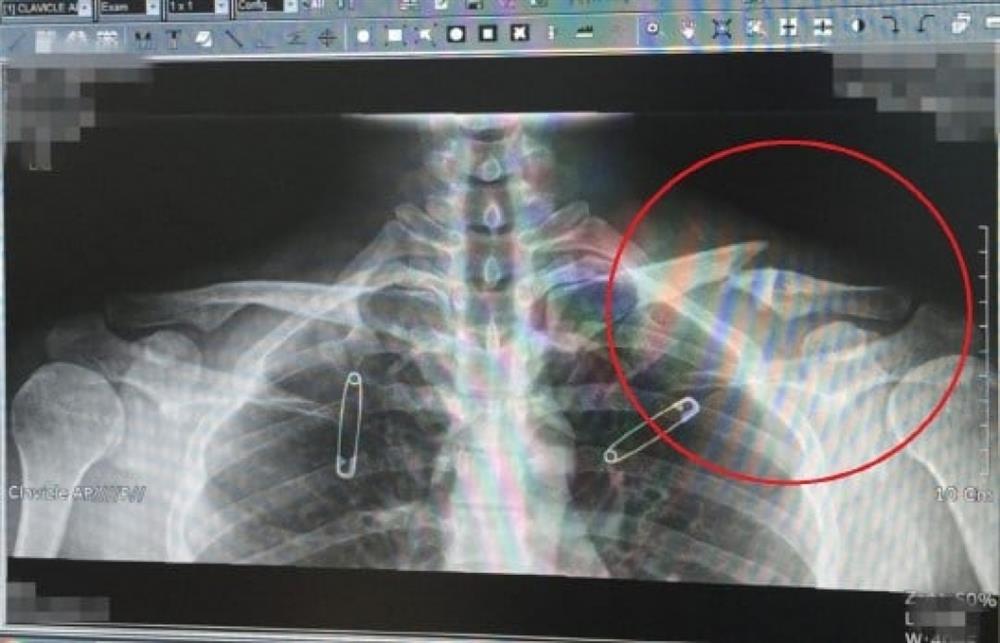

Vào năm 2017, nam diễn viên nhận được quyết định miễn nghĩa vụ quân sự vì các chấn thương và bệnh tật kéo dài. Trước đó anh cũng đã “trượt” các cuộc khám sức khỏe tới 5 lần.

Nhiều cư dân mạng đã chỉ trích Yoo Ah In một cách nặng nề, cho rằng anh giả bệnh để trốn thực hiện nghĩa vụ quân sự bắt buộc với quốc gia. Sau vụ việc này, hình ảnh nam tài tử bị ảnh hưởng nghiêm trọng.

''Thương tích đầy mình'', Yoo Ah In bị dân mạng ném đá nghi ngờ ''trốn'' nghĩa vụ quân sự